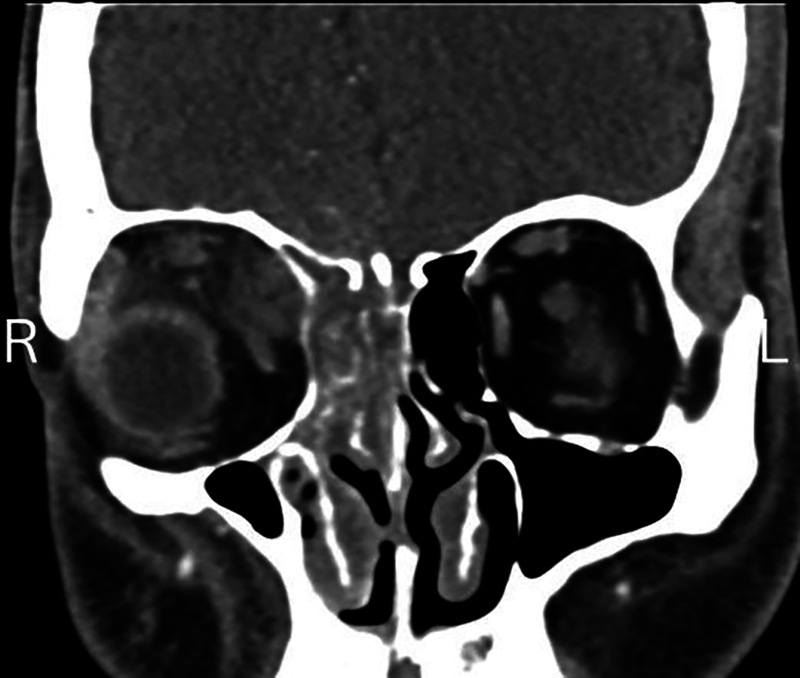

本病例报告一例29岁男性糖尿病患者并发鼻-眶-脑毛霉菌病(ROCM),经两性霉素B脂体眶内注射成功治疗。尽管紧急内镜清创,患者的疾病在颅内和眶内进展,但他拒绝进一步的手术干预。随后,由于急性视力迅速丧失,我们开始经皮球后两性霉素B (TRAMB)注射。注射后,尽管颅内进展,但视力、运动和眶内真菌负荷均有所改善。本报告强调了施用TRAMB治疗侵袭性真菌感染的益处,并探讨了其有效性背后的机制,特别是在全球保存方面。通过靶向血液供应相对稳定的区域的感染,TRAMB降低了手术难度并改善了总体结果。

This case report presents a 29-year-old male with diabetes mellitus who developed rhino-orbito-cerebral mucormycosis (ROCM) that was successfully treated with liposomal amphotericin B orbital injections. Despite emergent endoscopic debridement, the patient's disease progressed intracranially and intraorbitally, but he declined further surgical intervention. Subsequently, due to rapid acute vision loss, we initiated transcutaneous retrobulbar amphotericin B (TRAMB) injections. Following these injections, visual acuity, motility, and intraorbital fungal burden improved despite intracranial progression. This report highlights the benefits of TRAMB administration in aggressive fungal infections and explores the mechanisms behind its effectiveness, particularly in globe preservation. By targeting the infection in an area with a relatively robust blood supply, TRAMB reduces surgical difficulty and improves overall outcomes.